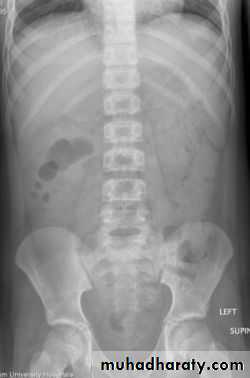

Positioning

• Supine AP

• Erect AP

• Lateral decubitus

The main purpose of horizontal beam films is to detect air-fluid levels and free intraperitoneal air

Intestinal gas pattern

Relatively large amounts of gas are usually present in the stomach and colon.The stomach can be readily identified by it's location, gastric rugae in the supine view and by the air fluid level beneath the left hemidiaphragm in the erect view